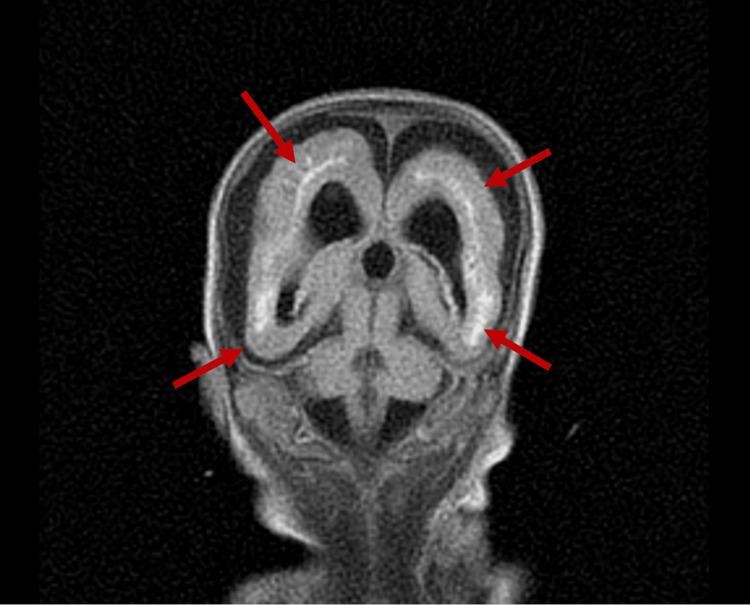

This case report investigates the management of a 24-week-old neonate with congenital cytomegalovirus (CMV) infection and its sequelae, including severe intrauterine growth restriction, thrombocytopenia, and brain anomalies, ultimately progressing to lissencephaly. The diagnostic challenges included delayed clinical suspicion of congenital CMV, which was not identified until after delivery through CMV DNA polymerase chain reaction, and differentiating its symptoms from other potential causes of the neonate's condition. Aggressive interventions included antibiotics, antiviral therapy with ganciclovir, and supportive measures such as intubation, CPR, respiratory support, blood transfusions, and management of coagulopathy. Despite these efforts, the patient deteriorated due to progressive hypoperfusion, hypoxemic cardiorespiratory failure, and disseminated intravascular coagulopathy. Due to the poor prognosis and extent of multiorgan damage, support was withdrawn per parental consent. This case highlights the complications encountered when managing an advanced-stage neonatal CMV infection and emphasizes the importance of a multidisciplinary and holistic approach to guide diagnosis and treatment.

本病例报告探讨了一名24周大先天性巨细胞病毒(CMV)感染新生儿及其后遗症的治疗情况,这些后遗症包括严重的宫内生长受限、血小板减少症和脑异常,最终发展为无脑回畸形。诊断面临的挑战包括先天性CMV的临床怀疑延迟,直到分娩后通过CMV DNA聚合酶链反应才得以确诊,以及将其症状与新生儿病情的其他潜在病因相区分。积极的干预措施包括使用抗生素、更昔洛韦抗病毒治疗,以及诸如插管、心肺复苏、呼吸支持、输血和凝血病管理等支持措施。尽管采取了这些措施,患者仍因进行性低灌注、低氧性心肺衰竭和弥散性血管内凝血而病情恶化。由于预后不良和多器官损伤程度严重,经家长同意停止了支持治疗。本病例突出了晚期新生儿CMV感染治疗中遇到的并发症,并强调了多学科整体方法在指导诊断和治疗方面的重要性。